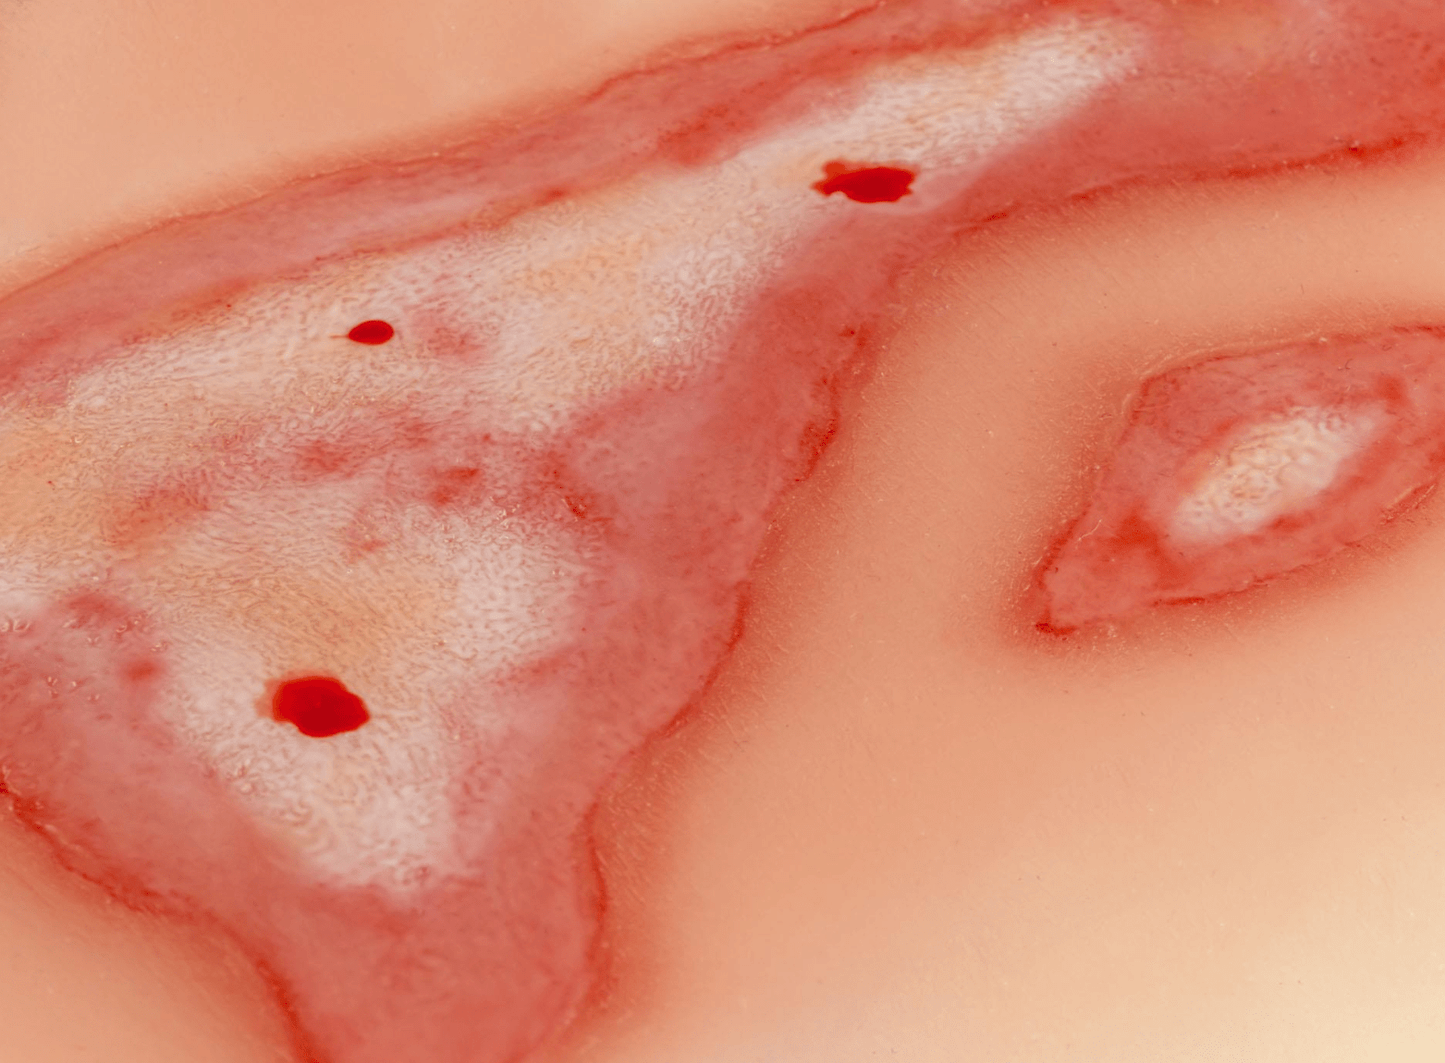

Unsere Wundmoulagen bieten eine äußerst realistische Darstellung verschiedenster Verletzungen und Wunden und sind daher unverzichtbare Hilfsmittel für medizinische Ausbildungen, Notfallübungen und Schulungen. Sie ermöglichen eine präzise und anschauliche Simulation von Verletzungen, die den realen Bedingungen in der medizinischen Praxis entsprechen. Die Moulagen sind aus weichem, hautähnlichem Material gefertigt, das keine Verletzungsgefahr darstellt und eine authentische Haptik bietet.

Durch ihre vielseitige Anwendbarkeit eignen sich die Wundmoulagen für die Übung von Wundversorgung, Verbandstechniken und Notfallmanagement. Sie haften selbstständig an Simulationspatienten oder Puppen, können jedoch bei Bedarf mit speziellem Hautkleber für längere Übungseinheiten befestigt werden. Jede Moulage wird mit einer praktischen Aufbewahrungsbox geliefert, die eine sichere und ordentliche Lagerung ermöglicht.

Simulation von Schnitt-, Riss- und anderen Wunden zur Übung der Wundversorgung

Realistische Darstellung von verschiedenen Wunden (z.B. Schnitt-, Riss-, Brand- oder Stichwunden)

Weiches, hautähnliches Material für eine authentische Haptik und Sicherheit